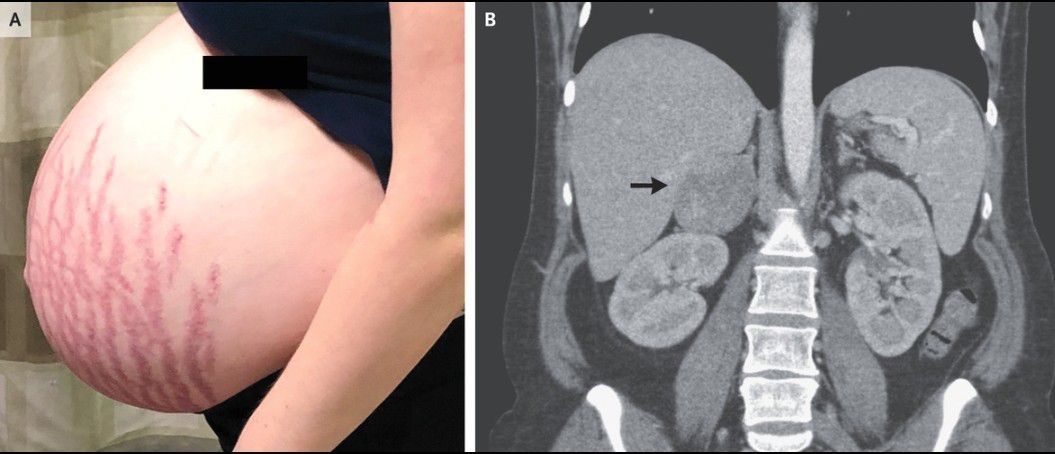

A 27-year-old primigravid woman was admitted to the hospital with new-onset diabetes and hypertension at 32 weeks of gestation. She reported that she had had worsening proximal muscle weakness, striae, and facial plethora for several months. Physical examination showed violaceous striae over the abdomen (Panel A), breasts, and dorsal and supraclavicular fat pads. Laboratory studies were notable for a potassium level of 2.9 mmol per liter (reference range, 3.5 to 5.5) and a urine protein:creatinine ratio of 24 (with protein measured in milligrams and creatinine in millimoles) (reference value, <30). An abdominal ultrasound examination, performed as part of the evaluation for Cushing’s syndrome, revealed a right adrenal mass that was 7 cm in length in its largest dimension. The level of free cortisol in the urine over 24 hours was 3058 nmol (reference value, <160). The patient’s hypertension was managed with labetalol and nifedipine; however, HELLP syndrome (characterized by hemolysis, elevated liver enzymes, and low platelet count) developed at 34 weeks of gestation. A healthy infant weighing 2890 g was delivered. A computed tomographic scan obtained without contrast material showed an adrenal mass measuring 6.8 cm in its largest dimension (Panel B, arrow) with a density of 22 Hounsfield units, a finding suggestive of adrenal carcinoma. Adrenalectomy was performed 1 month after delivery, and histopathological analysis confirmed the presence of high-grade adrenocortical carcinoma. An evaluation showed no evidence of metastatic disease, and treatment with adjuvant mitotane was initiated.